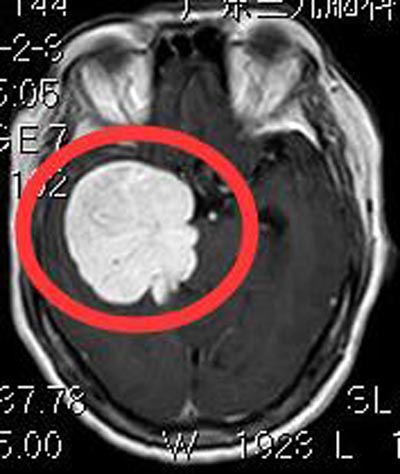

广东三九脑科医院头颅MR检查提示:鞍结节偏右侧占位性病变,大小约为51mm×60mm×48mm,考虑为脑膜瘤可能性大;头颅CTA检查提示:右侧颞部占位性病变,其内血管丰富(颈外动脉系统供血可能)。

▲术前MR